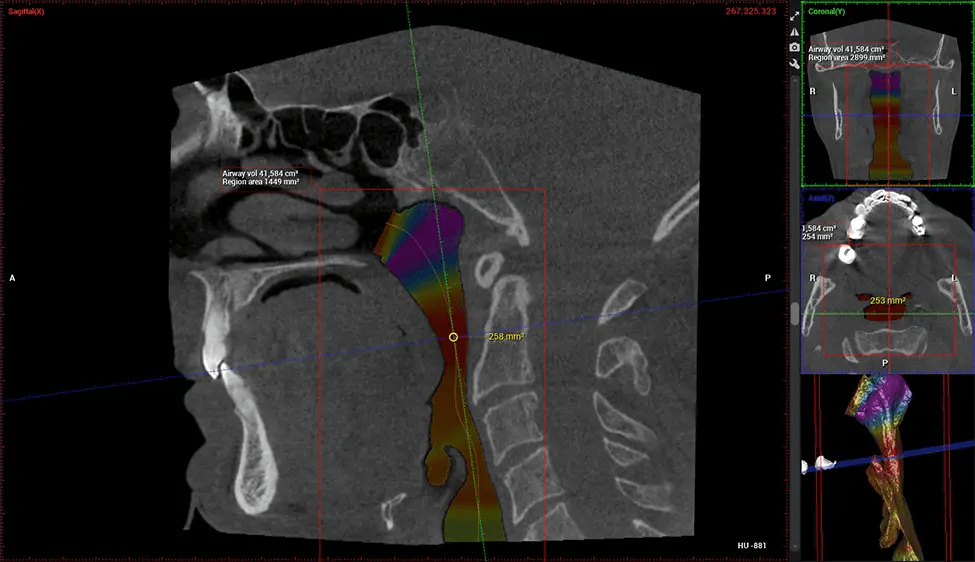

This 3D scan, called cone beam computed tomography, gives your dentist a more complete image of your oral anatomy and disease processes than a traditional X-ray. Unlike conventional X-rays, which capture a 2D image of your mouth from various angles, a 3D scan takes multiple digital X-rays for one image. It provides a complete view of your jaw, teeth, nerves, and soft tissues. This enhanced view allows dentists to detect minor issues not visible in traditional 2D scans, such as impacted wisdom teeth or bone fractures in the sinus cavity.

There are many benefits to using CBCT technology, especially compared to the traditional 2D X-ray format. One of the most significant advantages of CBCT scans is that they provide much more information than traditional X-rays. A scan lets your dentist see images from all angles of your jaw and mouth, including your sinuses, nasal cavity, cheekbones, and other surrounding areas. This added information helps your dentist craft a comprehensive treatment plan that addresses all aspects of your oral health.

After the scanning process, the captured X-ray images are processed by the CBCT software, which applies algorithms to reconstruct a detailed 3D image of the scanned area. The software compiles these individual X-ray images and creates a digital 3D representation of the patient’s anatomy. The reconstructed 3D CBCT image can be viewed and analyzed by the dentist or radiologist. This image can be manipulated, rotated, and zoomed in or out to examine specific structures and evaluate the patient’s condition.

Planmeca Viso G7 CBCT ( Cone Beam CT Scan ) is designed to surpass the demands of industry leaders, specialists, and large institutions. It’s has a large ø25×30 cm sensor with four built-in cameras. It can capture unlimited volume sizes from a ø3×3 cm to a ø30x30cm volume capturing the skullcap through C7 on the cervical spine. The Planmeca Viso G7 offers the industry’s largest single volume scan of ø30×19 cm. It’s poised to handle advanced imaging modalities such as Planmeca ProFace® and Planmeca 4D™ Jaw Motion technology. The occipital head support allows an unimpeded view of facial tissue.

Planmeca is the only manufacturer clinically proven to dramatically reduce patient radiation without sacrificing image quality. Planmeca Ultra Low Dose™ achieves an average reduction in dose of 77% without a statistical reduction in image quality allowing doctors to incorporate 3D imaging into routine protocols with effective patient radiation often lower than 2D intraoral imaging. This increases patient care, allows doctors to diagnose more dentistry, and often earlier in disease progression, than with 2D imaging alone.